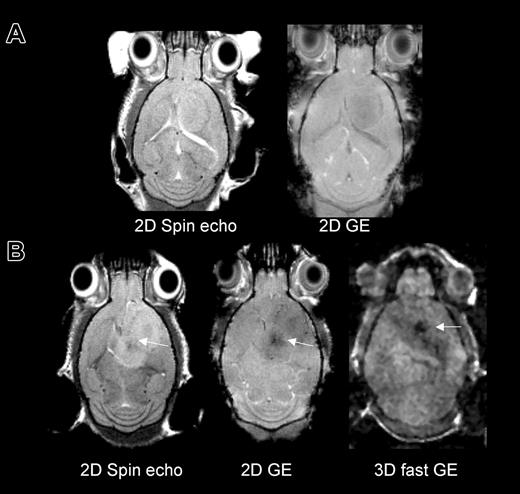

MRI was first performed in group 1 to assess the detectability of cells on different MRI pulse sequences. For this group, MRI was performed on day 12 following tumor implantation mice with magnetically labeled or unlabeled cells infused on day 5. A dark (hypointense) region as compared with contralateral “normal” brain was detected in the area within and surrounding the tumor on all sequences. The susceptibility effect progressively increased in intensity from a spin-echo to a fast gradient-echo sequence (Figure 1). Serial MRI studies to determine the time course were performed on groups 2 and 3. These revealed that in mice that received Sca1+ FE-PLL-labeled cells within 2 days of tumor implant, hypointense regions in the tumor initially appear at about 9 days from transplantation and ultimately appear to circumscribe the tumor rim evolving into a continuous dark ring. Figure 2 shows time course MRI performed from day 4 to 11 of a mouse that received labeled cells 2 days after tumor implant. At day 4 the needle tract from the tumor implantation was evident on MRI; there were no other hypointense effects. At 9 days, a slight hyperintense area around the original needle tract is observed which is indicative of edema from growing tumor. Hypointense areas compared with contralateral hemisphere were also observed at this time point in and around the tumor. At day 11, a ring around the tumor was observed (Figure 2), on both in vivo and ex vivo MRI. Linear projections into the center of this tumor were also observed in vivo and were clearly delineated at higher resolution on ex vivo MR. Five of 6 mice that were infused with FE-PLL-labeled cells and imaged 10 or more days later exhibited a hypointense ring surrounding the tumor.

MRI in mice that received either no cell transplant or magnetically labeled Sca1+ bone marrow cells at day 5 of tumor growth and were imaged 7 days later to investigate detection of labeled cells by several MRI techniques. (A) Mouse with 12-day tumor and no cell transplant on 2D spin echo and gradient echo (GE) images. (B) Mouse with 12-day tumor and 7 days from labeled cell transplant on spin echo, GE, and fast GE images. Hypointense areas in the tumor were detectable with all sequences in the labeled mouse. The fast gradient echo had the greatest sensitivity to iron and the least anatomic definition.